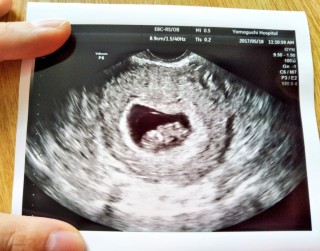

2週間前の検診で3mmだったベビたんが19.3mmになってた!!お手手振ってくれたりとっても可愛い子( ¨̮ )これからもっともーっと大きく成長してってね!!

つわりがひどく、便秘気味のため赤ちゃんが心配でしたが、スクスクと育っててくれて安心! 2週間前は、まだ小さかったのに急激に大きくなる我が子をみて微笑ましくなりました笑 まだまだつわりがありますが、頑張っていこうと思います🙂

一週間前は7.6mmだったのですが7日間で19.3mmまで成長していて二頭身で少し人間らしくなっていました!!まだ出産までの道のりは長いけど少し安心しました。